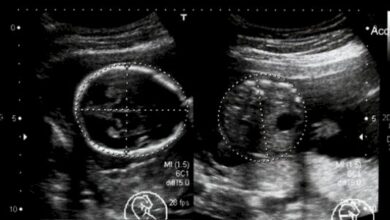

هُنالِكَ العديد من الطُّرق المُستخدمة للاستماع إلى نبضات قلبِ الجنين، أفضلها بالطبع هيَ عن طريق مُراجعةِ الطّبيب والاستماع لنبض الجنين عبر فحص الدوبلر للجنين، ولكن هل يمكن الاستماع لنبض الجنين بالبيت؟

• الحصول على جهازِ العرض: فبالإمكان شراءِ شاشاتٍ رخيصةٍ نسبياً لسماع ورؤيةِ قلب الجنين واستخدامها في المنزل، وتُعدّ هذهِ الوسيلةُ فعّالةً للأمّهات المُعرّضات للإجهاض؛ بحيث يُمكنهُنَّ الاستماع إلى نبضاتِ القلب والاطمئنان في الفترةِ المُمتدّة ما بين كُل زيارة وأُخرى للطبيب. ولكن يجب العلم بأنَّ هذهِ الأجهزةِ ليست فعّالةً وجيّدةً كتلك الموجودة في عيادةِ الطّبيب، ولن يكونَ الصّوت واضحاً ونقيّاً إلّا إذا كانَ الحَمْل في الشّهر الخامس تقريباً.